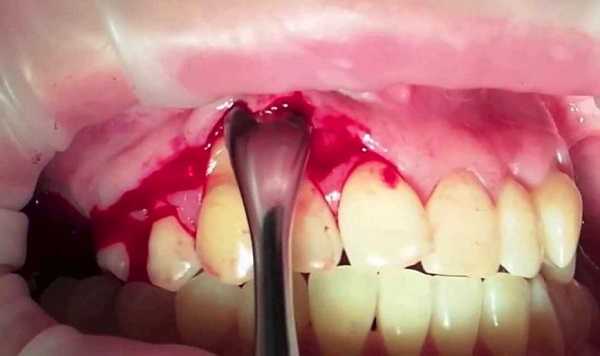

Цистотомия

Операция проводится под местной анестезией по следующей схеме: хирург выкраивает полуовальный слизисто-надкостничный лоскут в проекции кистозного образования, обнажает костную стенку и проводит трепанацию, после чего полость кисты промывается и заполняется тампоном с йодоформом. Для профилактики рецидива в ходе операции рекомендуется произвести тщательную ревизию тканей и удалить некротизированные участки. Через 7 дней необходимо сменить тампон и в дальнейшем производить смену повязки 3-4 раза. Данное вмешательство хорошо переносится пациентами, но сопровождается длительным существованием послеоперационного дефекта.